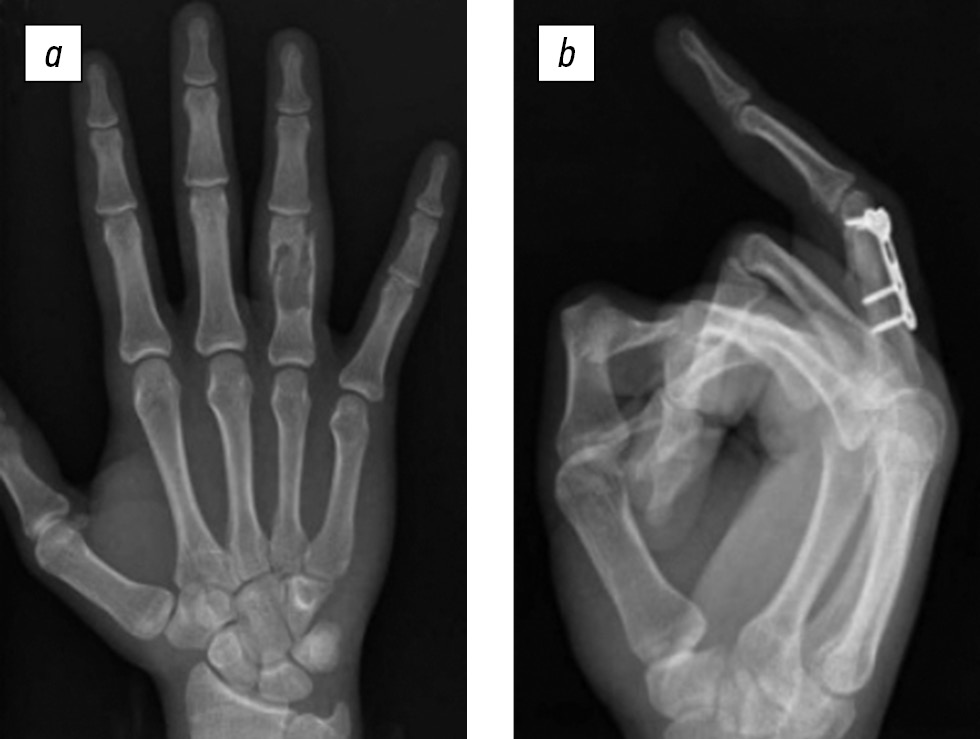

Пример раннего хирургического лечения представлен на рис. 3, а (пациент с патологическим переломом проксимальной фаланги IV пальца на фоне энхондромы). Рентгенологически в центральной части проксимальной фаланги IV пальца отмечено разрежение костной ткани с истончением кортикального слоя и нарушением его целостности с двух сторон. Выполнено оперативное лечение (рис. 3, b) — кюретаж энхондромы с замещением дефекта аутотрансплантатом из гребня подвздошной кости с фиксацией пластиной, винтами.

Рис. 3. Пациент 17 лет со смещенным патологическим переломом проксимальной фаланги. © Çapkin S. и соавт., 2020. Распространяется на условиях лицензии CC BY-NC 4.0. Источник: заимствовано из [DOI: 10.7759/cureus.7497].

Тактика раннего хирургического лечения позволяет сократить сроки нетрудоспособности, обеспечить раннюю гистологическую верификацию патологического образования и снизить риск консолидации в порочном положении. Однако существует риск развития осложнений в виде вторичного смещения фрагментов, несостоятельности металлоконструкции, миграции костнопластического материала в мягкие ткани [2, 46, 58].